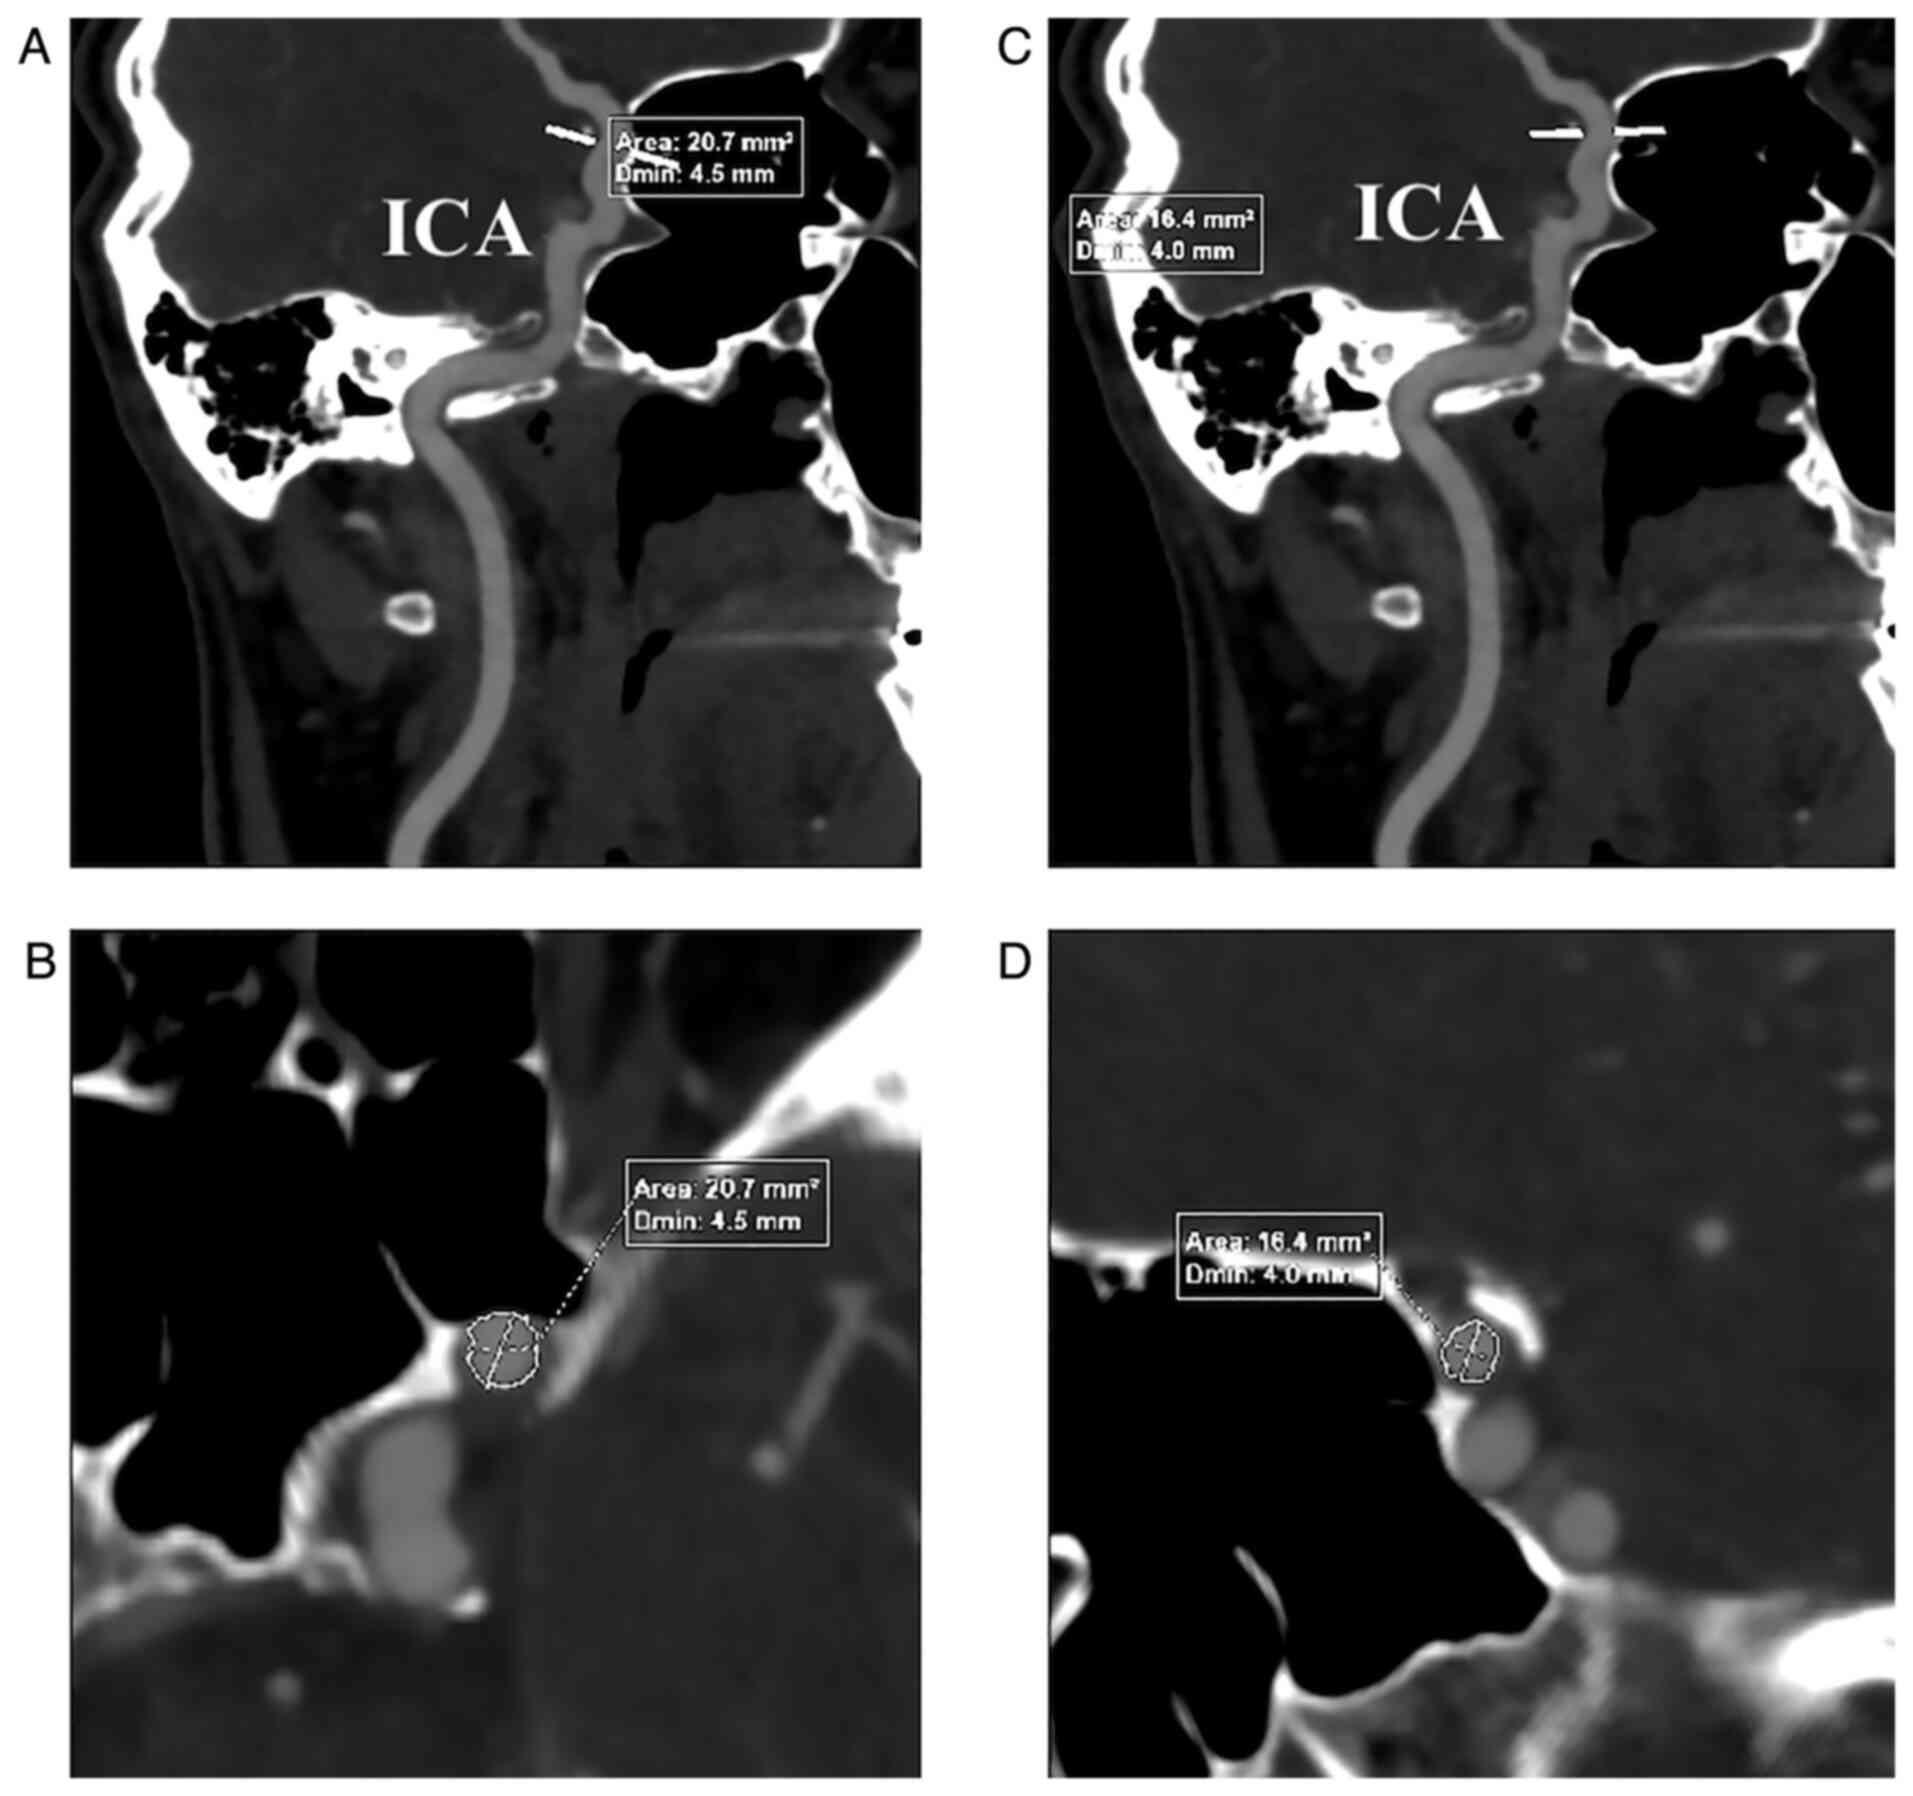

Morphometric study regarding ophthalmic and internal carotid arteries utilizing computed tomography angiography

The aim of the present study was to accurately measure the diameter of the ophthalmic artery (OA) and investigate whether bilateral variations in diameter can be recorded in relation to patient age and sex. A retrospective study including 80 computed tomography angiographic (CTA) examinations and a total of 160 arteries was conducted to demonstrate the morphometric aspects of the OAs analyzed bilaterally by CTA examinations, while considering the references of the internal carotid artery (ICA) caliber. Precise measurements performed on the OA and the ICA below and above the ophthalmic emergence revealed an OA diameter of 1.38±0.24 mm and a narrowing of the ICA between the origin of the OA of 1.5±0.25 mm. Variations in the OA and the ICA calibers were studied in subjects with normal cervical vasculature on CTA. After a thorough statistical study, variations in OA and ICA caliber on each side were identified, between both sex and age‑related groups, revealing morphometric parameters of the OA in relation to the ICA.